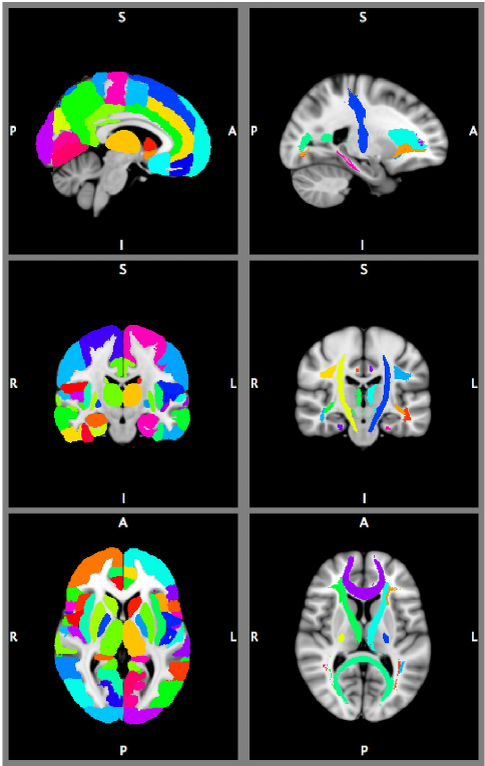

Атласы мозга широко используются при визуализации мозга, чтобы связать структурную или функциональную метку с положением в системе координат, часто определяемым в пространстве опорного сигнала мозга, таком как MNI 305. Атласы, как правило, состоят из серии изображений или одного разделенного изображения, типичного или усредненного мозга. Они используют либо жесткие метки (ноль, одна или несколько меток для данной позиции), либо вероятностную информацию, указывающую на вероятность наличия метки в определенном месте. Атласы существуют как для 3D, так и для поверхностной геометрии и могут представлять различные типы информации (например, цитоархитектоническая или анатомическая макроскопическая сулькогиральная информация, функциональная информация и т.д.). Хотя большинство исследователей в области нейровизуализации обычно используют один или несколько атласов мозга в своем анализе, формат данных этих атласов различается. Это означает, что для извлечения информации будет необходим специализированный процесс, а сравнение результатов анализа будет затруднено. Например, Harvard-Oxford (HO), Automatic Anatomical Labelling (AAL), Freesurfer и JuBrain относятся к наиболее часто используемым атласам и не представляют метаданные или другую информацию в едином формате. Также растет число других функциональных разделов и атласов функциональных сетей.

Хотя атласы мозга широко распространены и их число растет, на текущий момент не существует стандартного способа описания содержащейся в них информации, даже для очень похожих типов атласов, таких как HO и AAL. Это неэффективно для разработчиков и приводит к возникновению ошибок, затрудняя комбинирование атласов и осложняя проведение экспериментов и сравнений данных. В более широком смысле, отсутствие четкого описания и формата делает неясной концепцию атласа (по сравнению с шаблоном или системой координат).